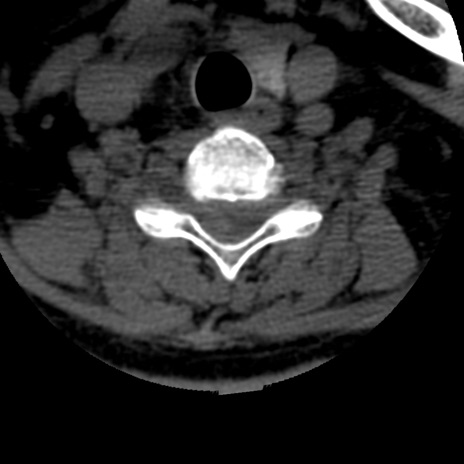

症例50 頚椎CT(横断像)

【症例】60歳代女性

【主訴】後頭部〜右後頸部にかけての痛み

【現病歴】本日飲食店でコーヒーを飲んでいたところ、突然後頭部〜右後頸部にかけて痛みが出現し、右上肢の感覚障害を伴ったため救急要請。

【身体所見】脳神経学的に明らかな異常所見を認めず。右上肢に軽度の感覚障害あり。

異常所見と診断は?

頚椎CT